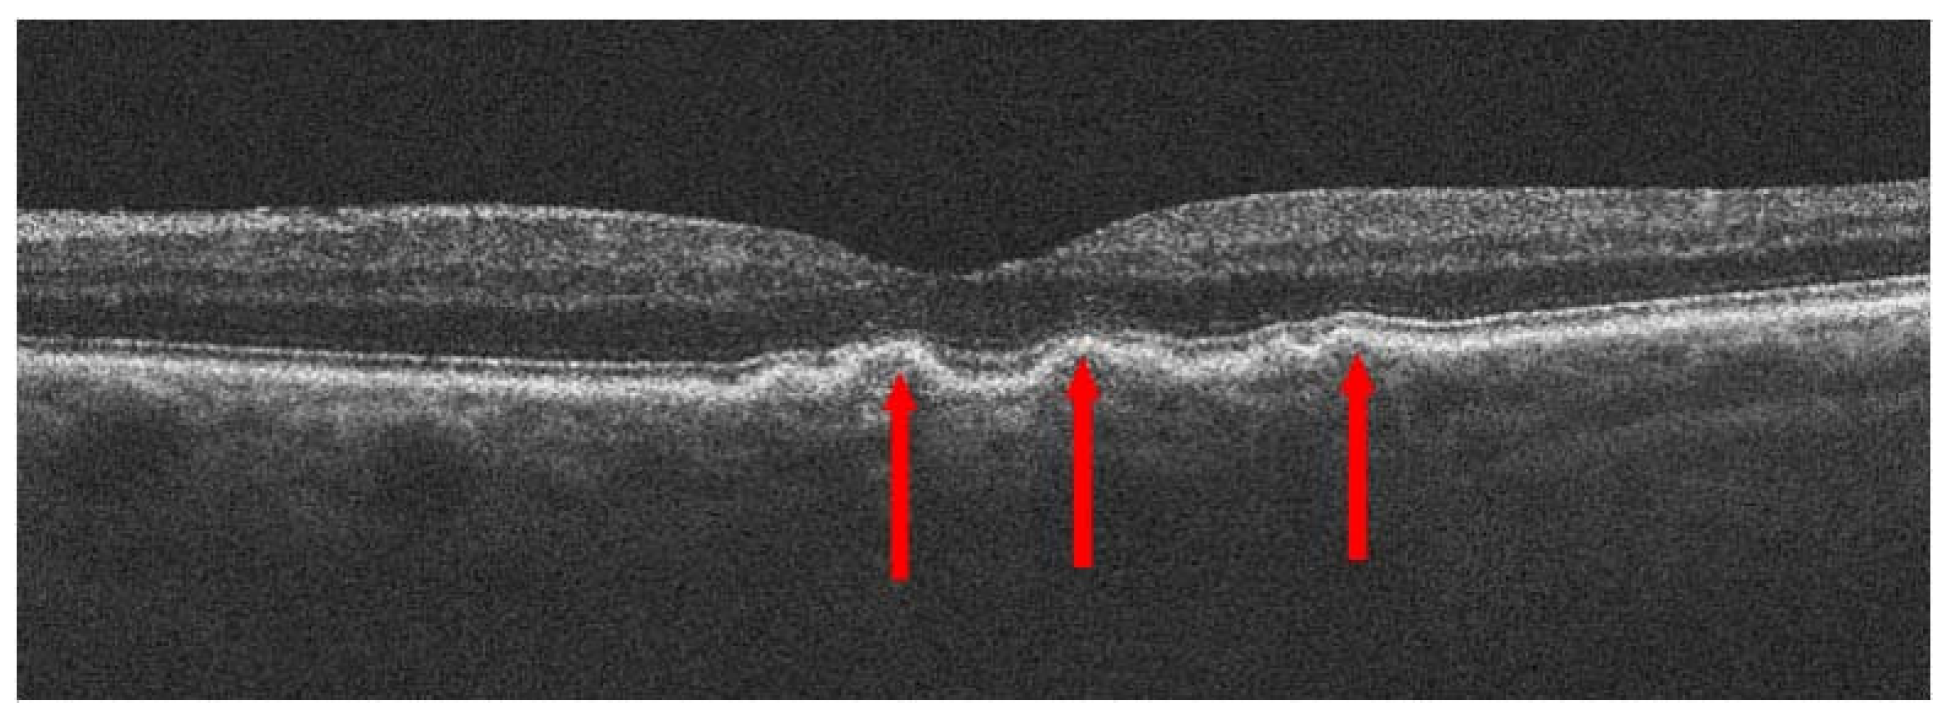

2. Treatment of Dry AMD

2.1. General Information

2.2. Drugs in Dry AMD